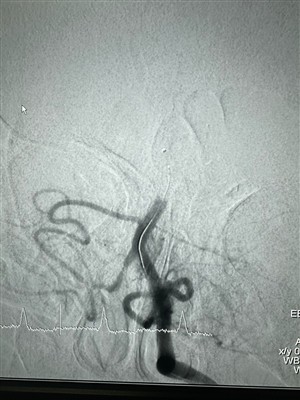

Casos de uso do sistema embólico líquido LAVACompartilhe uma cirurgia intervencionista recente que foi concluída usando o Sistema Embólico Líquido LAVA da NeuroSafe.

Mais -

Um caso usando o sistema embólico líquido LAVA na EspanhaPaciente do sexo masculino, com 64-anos, com AAA infrarrenal (diâmetro máximo de 79 mm) rompido e tratado com EVAR. Em angiotomografia controle um ano depois, preenchimento de contraste e crescimen...